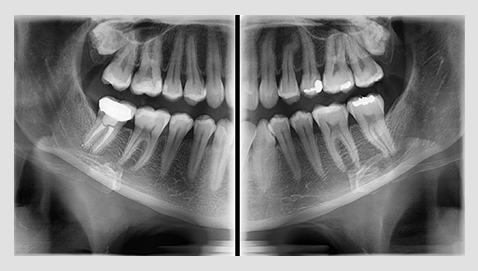

The PaX-i provides precise high-quality panoramic image by combining image processing and accumulated experience in dental imaging from VATECH. This will improve your diagnostic accuracy by increasing treatment planning and patient satisfaction.

A clear and sharp panoramic image brings you better diagnostics.

Advanced details, especially in the anterior and roots, can easily be viewed with the PaX-i.

These consistently high-quality images are the new standard of panoramic imaging.